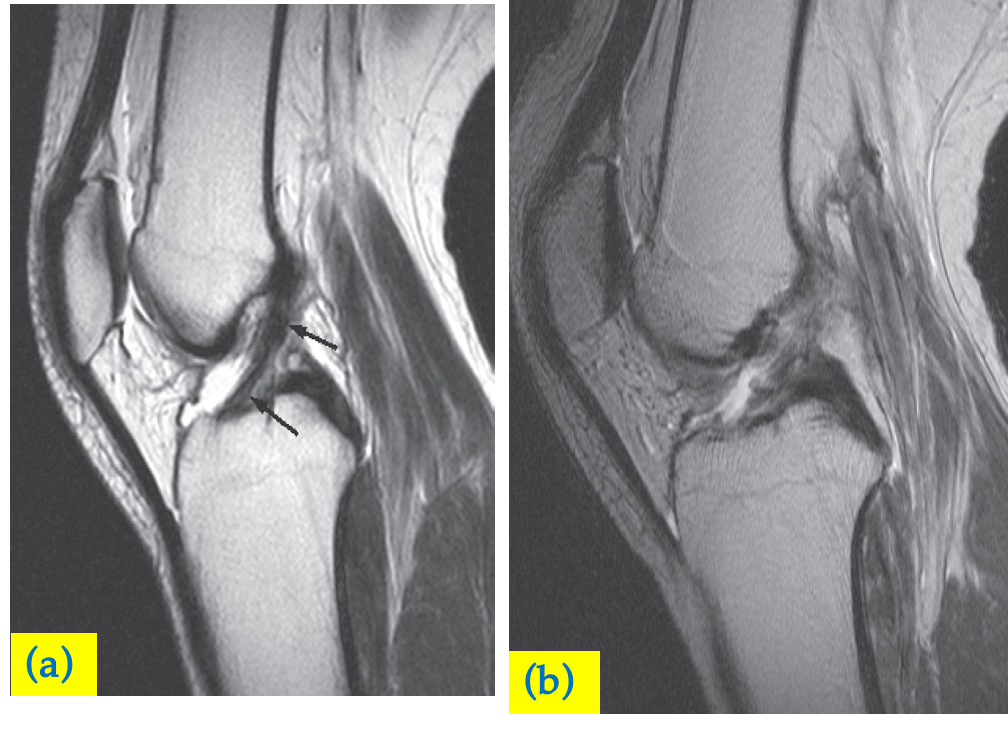

(a) Normal anterior cruciate ligament is shown as a low signal band in the intercondylar notch (arrows) on this MRI scan.

(b) With a tear the ligament is disrupted.